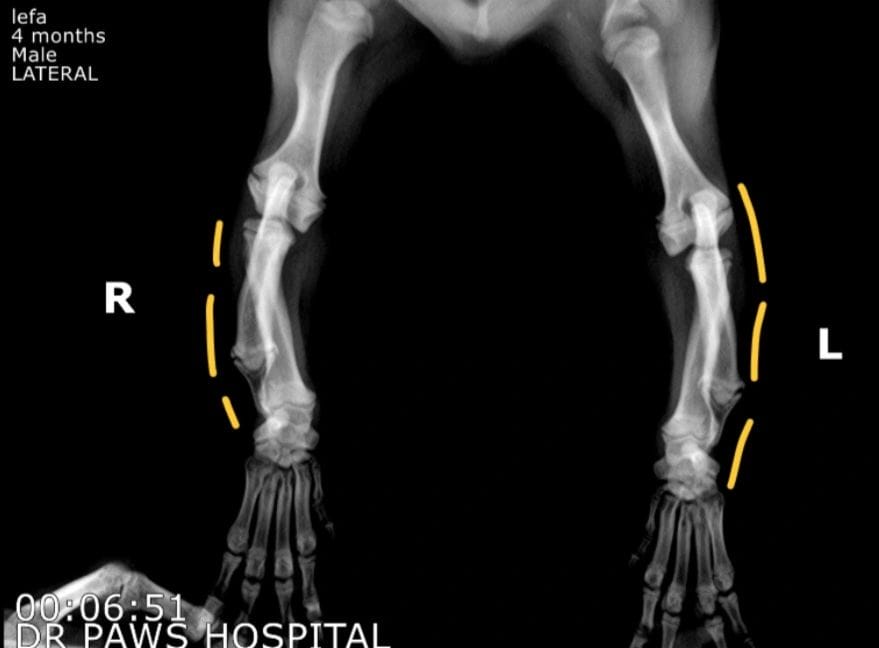

تم عرض كلب داشهوند عمره 7 أشهر، يعاني من تشوه فالكوس ثنائي الجانب، وهو سوء محاذاة لمفصل الكوع يحدث نتيجة قصر عظمة الزند، مما يؤدي إلى انحناء مفصل الرسغ جانبيًا.

الفحوصات والأشعة

الأشعة السينية أكدت وجود متلازمة الزند القصير (Short Ulna Syndrome)، وتم إجراء القياسات اللازمة لتخطيط جراحة قطع الزند (Ulnar Osteotomy)، بهدف توفير مساحة لنمو عظمة الكعبرة الحاملة للوزن وإطالة العظم.